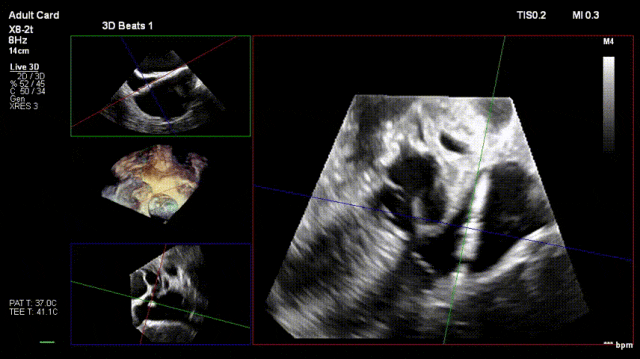

2. Steer and rotate the delivery system toward the target; advance and deploy the anchoring screw under 3D MPR plane guidance

3. After adjusting orientation, position the clamping arms for landing